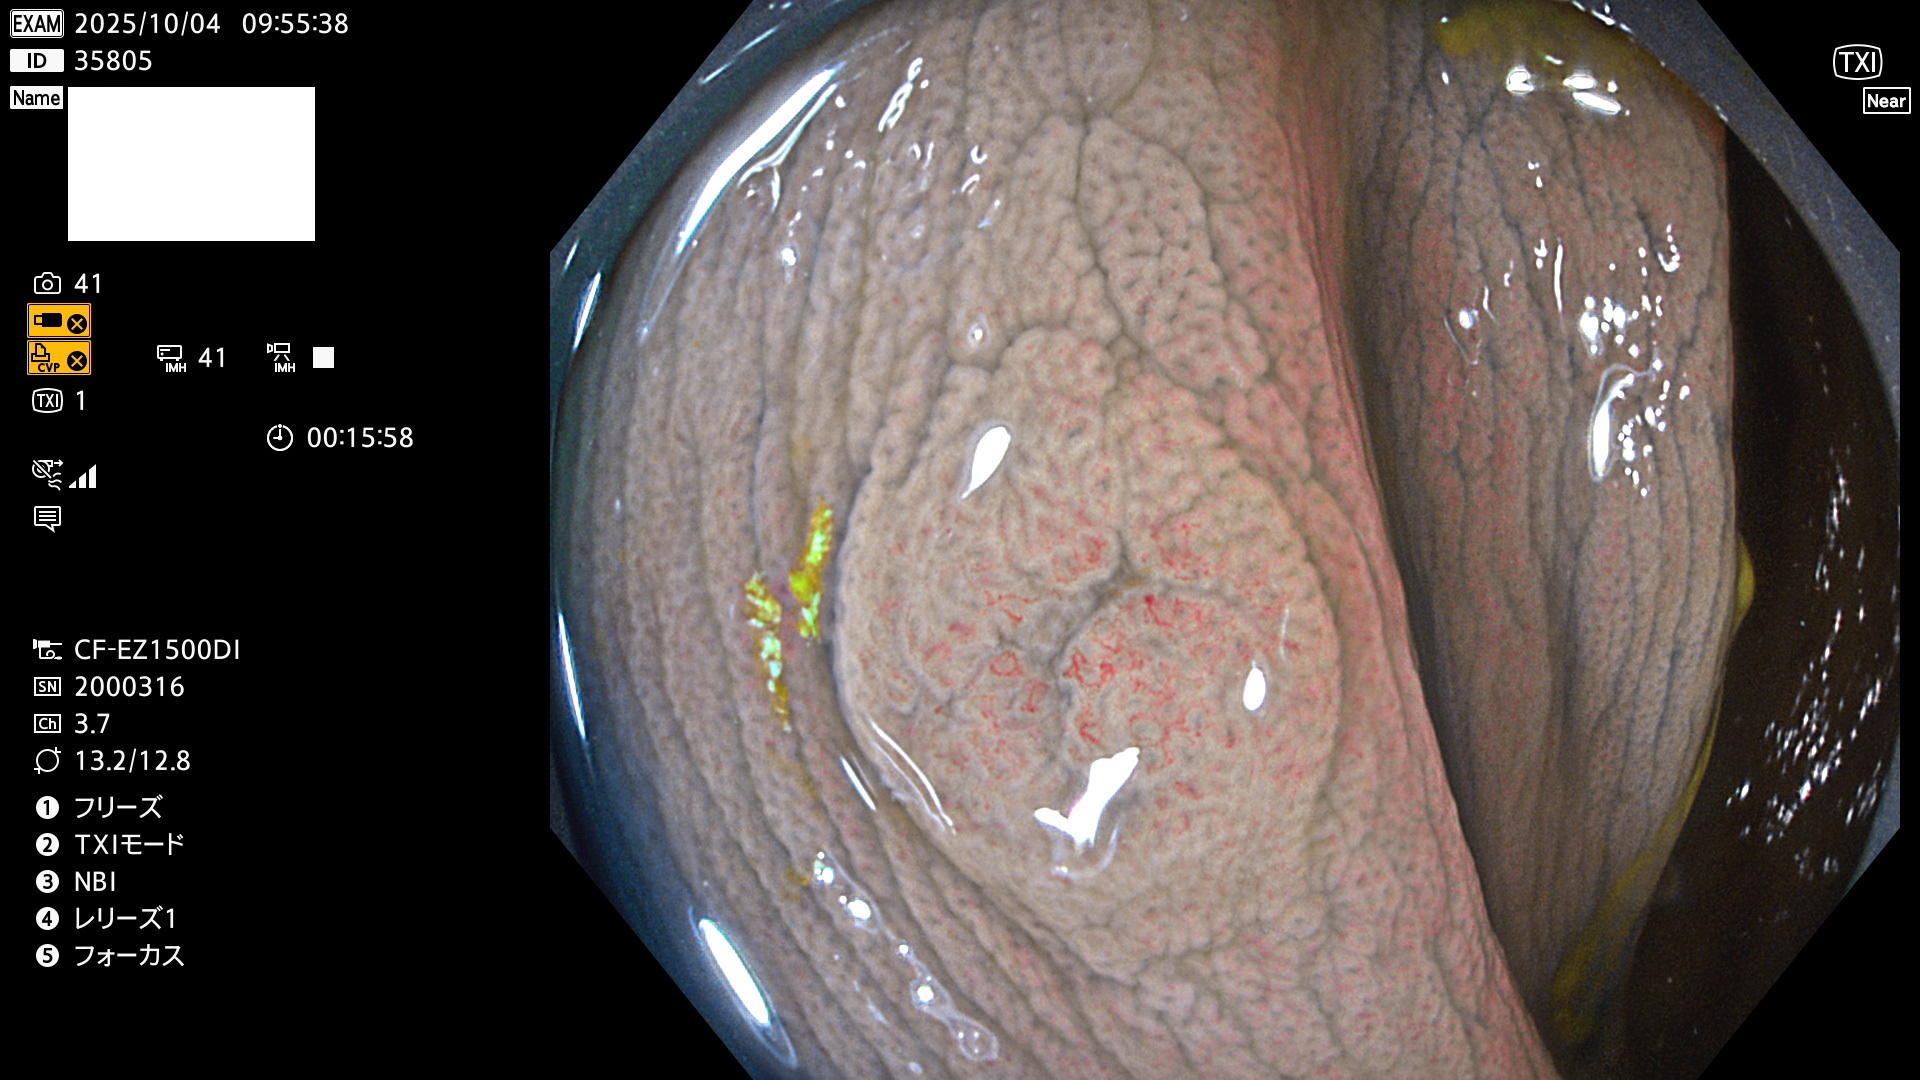

完全に平坦な物をUb、陥凹している物をUcと呼びます。Ubは認識が困難で、Ucはびらん(炎症)と紛らわしいために見落とされやすく、「内視鏡後・大腸癌」の原因になります。

専門的)Uc=De Novo癌? 内視鏡の解像度が低かった時代、このような説もありました。しかし今日の高精度内視鏡では良性の微小なUc型腺腫(APC遺伝子異常の腺腫)が日常的に見つかります。Ucこそが多段階発癌(Adenoma-Carcinoma Sequence)のMain Routeです。

毎週の検査(木・金・土・日)に発見されたUbとUc型・腺腫を、その週の日曜の夜にUPし1週間、提示します。

2025年10月2日〜10月5日の4日間(40件)9個 (Uc_ADR=9個/40人=23%)